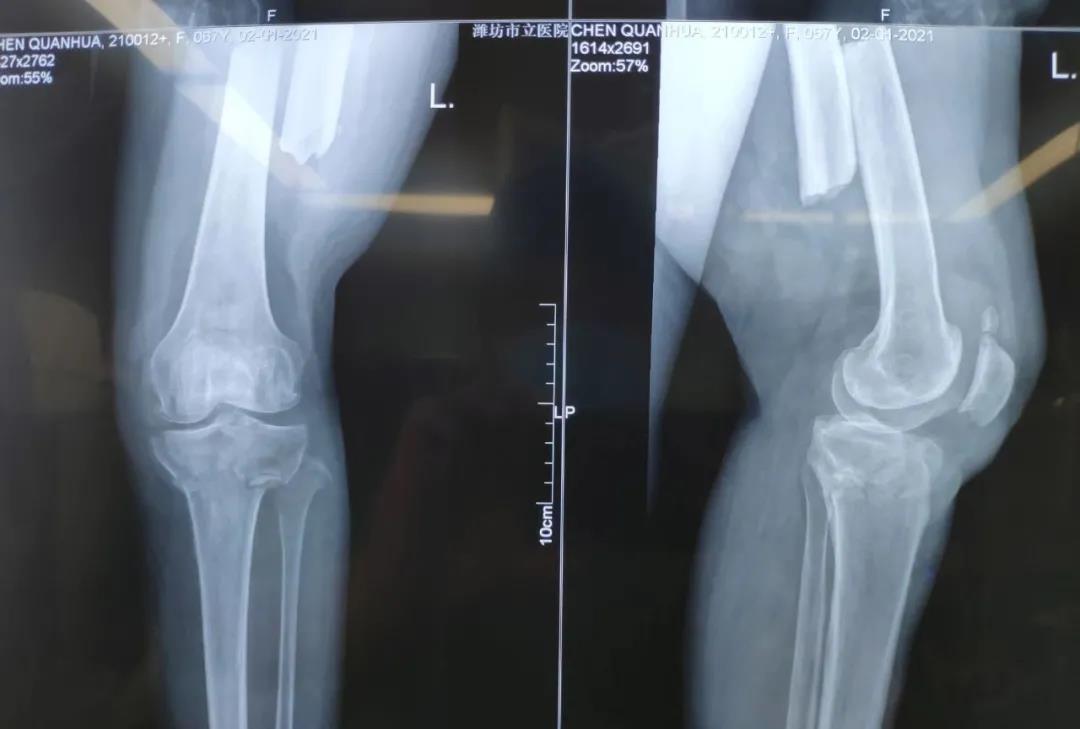

2021年1月2日下午,濰坊市市立醫(yī)院急診科接收了一位67歲的阿姨,阿姨是一位環(huán)衛(wèi)工人,在路邊清掃積雪時(shí)不慎被一輛汽車撞傷,致使其左脛骨平臺(tái)骨折、左股骨干骨折、左橈骨骨折,急需手術(shù)治療。

在快速做好精密的術(shù)前準(zhǔn)備后,2021年1月2日晚,創(chuàng)傷外科孫守全主任團(tuán)隊(duì)為阿姨行左脛骨平臺(tái)骨折、左股骨干骨折、左橈骨骨折切開(kāi)復(fù)位內(nèi)固定術(shù)手術(shù),手術(shù)順利。術(shù)后阿姨的病情得到穩(wěn)定,在醫(yī)務(wù)人員的貼心服務(wù)和細(xì)心照料下,身體恢復(fù)狀態(tài)良好。